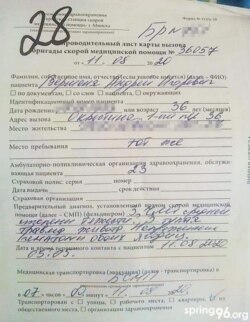

Пасьля вызваленьня Кірыл зьвярнуўся ў лякарню, дзе яму дыягнаставалі пералом правай ступні, пашкоджаньні левага пляча і перадплечча, правага сьцягна. Некаторы час ён прабыў у гіпсе.